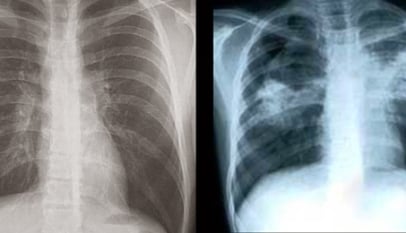

diabetes tuberculose carlos couri

Diabetes-Tuberculose: epidemia silenciosa e desconhecida!